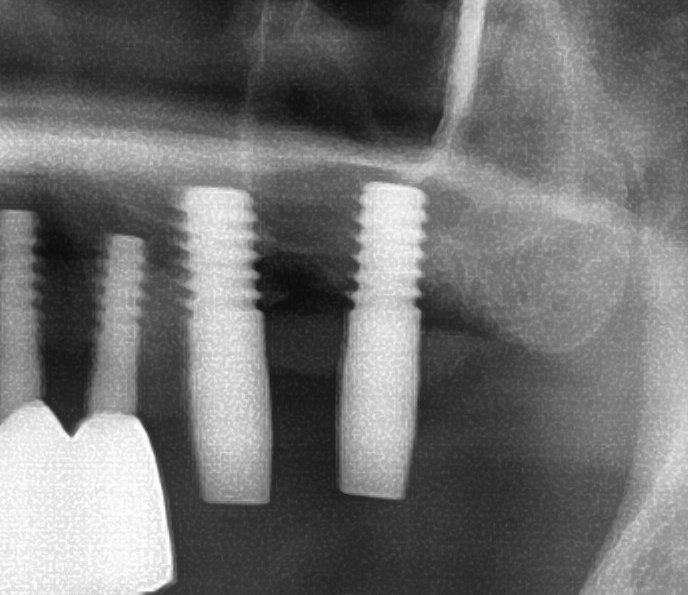

今回の患者様はインプラント植立を希望され、左上6番目・7番目の2本の植立が決まりました。

続けて左上7番も同じように植立していきます。

インプラントオペでは、複数本を植立する場合でも、当時進行はせず、1本ずつ同じ工程を繰り返して植立します。

しっかりとインプラント埋め込まれた後は、動揺がないか、噛んだ時に当たらないかなどを確認して、最後にパノラマ写真を撮影して今回のオペは終了となりました。